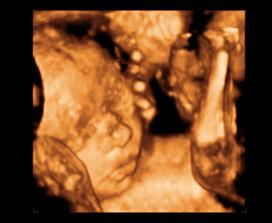

26 tt../1.4.2009/ naša paulínka je stráášne zlatá, boli sme si pozrieť na 4D utz. ..tvárila sa veľmi dôležito, až nafúkano...hehe..vôbec sa nechcela usmievať... nakoniec sa nám aj zasmiala...v brušku veľmi vyvádza, maminke dosť vytláča všetky časti telíčka, čo je niekedy aj dosť bolestivé...ale vydržíme, drobečkovi je tam určite tiež pritesno..a ešte aj stále viac a viac bude... strááášne sa na ňu tešíme🙂))